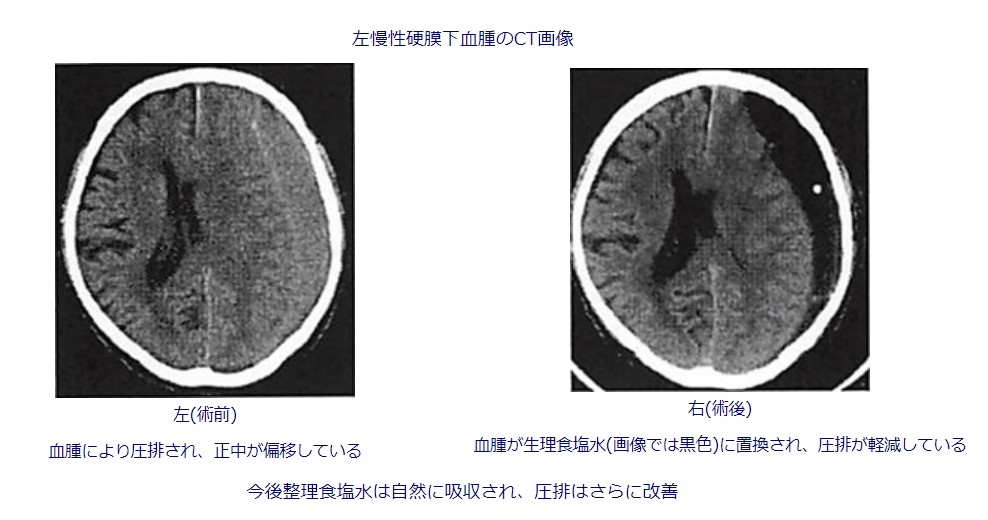

当院では主に穿頭血腫洗浄術を行っております。局所麻酔下(痛み止めの皮下注射)と鎮静薬を用います。頭蓋骨に一円玉程度の穴を開けてドレナージチューブを挿入し、血腫を吸引した後に洗浄します。再発抑制目的に血腫腔内にドレーンを留置して手術終了とする場合がほとんどですが、これは通常術後1~2日目で抜きます。